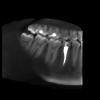

Bier Опубликовано 25 июля, 2012 Поделиться Опубликовано 25 июля, 2012 у вас судя по всему свищ открылся, на этих картинках я патологию не усмотрел...надо бы зайти к врачу, вставить в свищ гуттаперчу и сделать прицельный снимок З.Ы. КТ целиком не смотрел 1 Ссылка на комментарий

netdog Опубликовано 25 июля, 2012 Автор Поделиться Опубликовано 25 июля, 2012 (изменено) ещё не пойму что за белые точки на верхних зубах....не судите снимки строго я их делал сам! Прогой впервые пользуюсь! Лучше смотрите если есть время кт полностью) но все ровно спасибо! Bier спасибо за комментарии!Про свищ мне сегодня тоже что-то говорили ( я сегодня был у врача, просто на осмотре, записался на субботу ) Изменено 25 июля, 2012 пользователем netdog Ссылка на комментарий

kriokov Опубликовано 26 июля, 2012 Поделиться Опубликовано 26 июля, 2012 +1 к Bier, на одном из сканов похоже на ход от свища в обл 5. Навряд ли такие проявления от 8 1 Ссылка на комментарий

АнтонТЛТ Опубликовано 2 августа, 2012 Поделиться Опубликовано 2 августа, 2012 А вот ещё около 4 рядом с 5 чуть ниже какое то потемнение, это надеюсь не киста?Не киста, это ментальное отверстие место выхода сосудисто-нервного пучка из челюсти+1 к Bier, на одном из сканов похоже на ход от свища в обл 5. Навряд ли такие проявления от 8не похоже на свищ это скорее сосуды в кость входят, это же язычная сторонаhttp://i026.radikal.ru/1208/8d/08cbf45a53e4.jpgТам еще есть такие входыhttp://s017.radikal.ru/i433/1208/2e/fbe2e4941db9.jpg Ссылка на комментарий